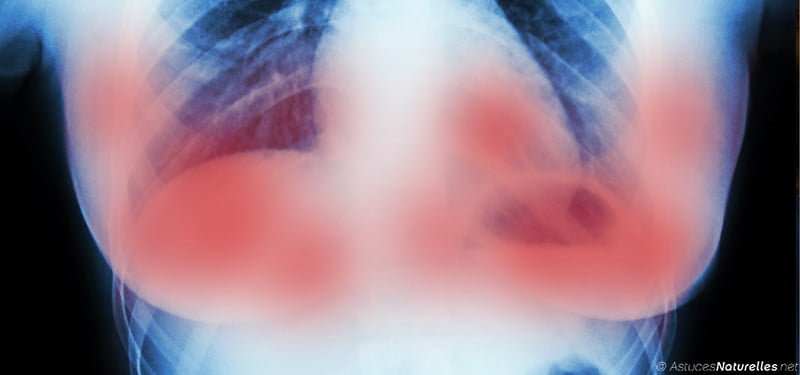

Une équipe de scientifiques a présenté les résultats de certains essais cliniques qu’ils ont réalisés dans le cadre du traitement du cancer. Et si ces résultats s’avèrent concluants, cela pourrait bien marquer un tournant décisif dans la lutte contre le cancer, plus spécifiquement contre le cancer du sein.

Lors de la Conférence européenne sur le cancer du sein à Amsterdam, le professeur Nigel Bundred a présenté les résultats d’une recherche récente qui a permis d’évaluer les effets de deux médicaments, l’Herceptin (trastuzumab) et le Lapatinib dans le traitement du cancer du sein.